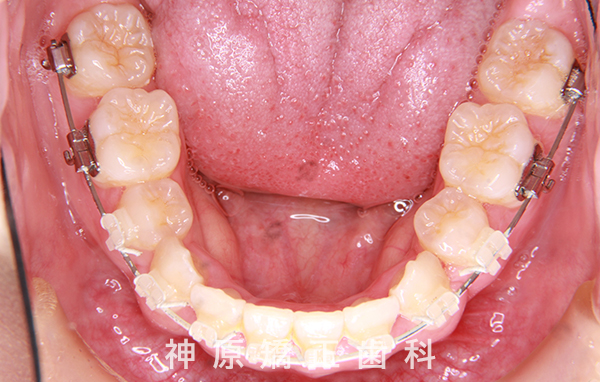

治療経過1年後